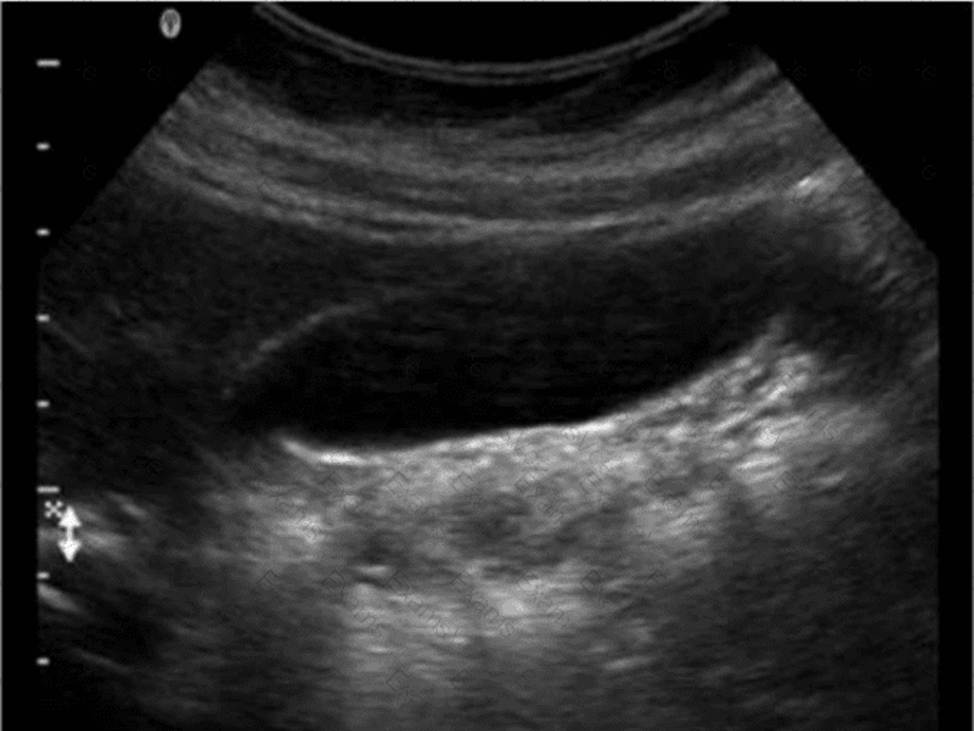

Which technique is used to demonstrate the finding in this video?

The technique shown in the video is compression. In ultrasound imaging―especially of soft tissue masses, the bowel, or venous structures―compression is used to evaluate the compressibility of structures. The image demonstrates a classic grayscale ultrasound view of a lesion or structure being compressed with the probe.

Compression sonography is particularly important in:

Evaluating venous patency (e.g., for deep vein thrombosis)

Differentiating cystic from solid structures

Evaluating bowel wall abnormalities or intussusception

Assessing lymph nodes and soft tissue masses (as shown here)

When a structure compresses easily under probe pressure, it suggests that the lesion is fluid-filled or soft. In contrast, incompressibility may indicate a solid mass or thrombus.

Differentiation from other options:

B. Valsalva: Involves forced expiration against a closed airway, used primarily to assess venous reflux or inguinal hernias―not what is demonstrated here.

C. Exhalation: A respiratory maneuver that passively alters thoracoabdominal pressure, not actively performed by the operator or causing focal structural change.

D. Deep inspiration: Used to improve visualization of the liver, diaphragm, or gallbladder―not to evaluate the compressibility of soft tissue.